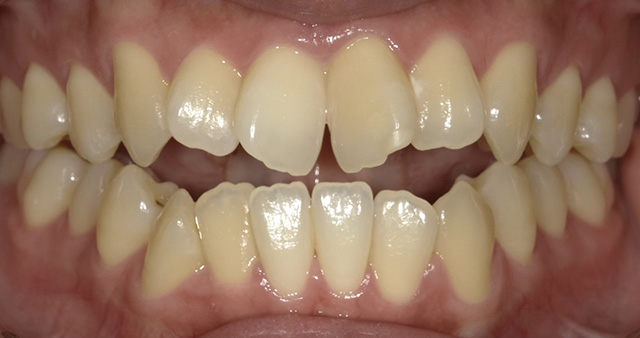

上顎(じょうがく)の糸切り歯(犬歯)が歯並びから飛び出している状態を八重歯(やえば)といい、歯並びが凸凹(でこぼこ)になっている状態を、乱ぐい歯といいます。これらは歯並びが悪い状態を指し、叢生(そうせい)とも呼ばれています。顎(あご)が小さいと歯が生える十分なスペースがないため、歯と歯が重なり合って、叢生が生じると考えられています。叢生は、歯みがきの時に歯ブラシが届きにくく、歯と歯の間に食べかすがたまり、むし歯や歯周病が起こりやすくなります。

現在の矯正歯科の治療技術は進歩しており、成人の方でも無理なく矯正治療を行えるようになっています。確かに、お子さんの方が成長期にあるためスムーズに治療を行うことができますが、成長期以降の成人の方でも、多少時間はかかるものの、歯並びや噛み合わせのお悩みを解決することは可能です。矯正の大きな目的には、見た目のコンプレックスの解消がありますが、そのほかにも、きれいな歯並びになることで、歯みがきがしやすくなり、むし歯や歯周病の予防につながります。また、噛み合わせが整うことで、筋肉や顎関節、歯周組織に余計な負担をかけずにすみ、全身の健康にもつながります。